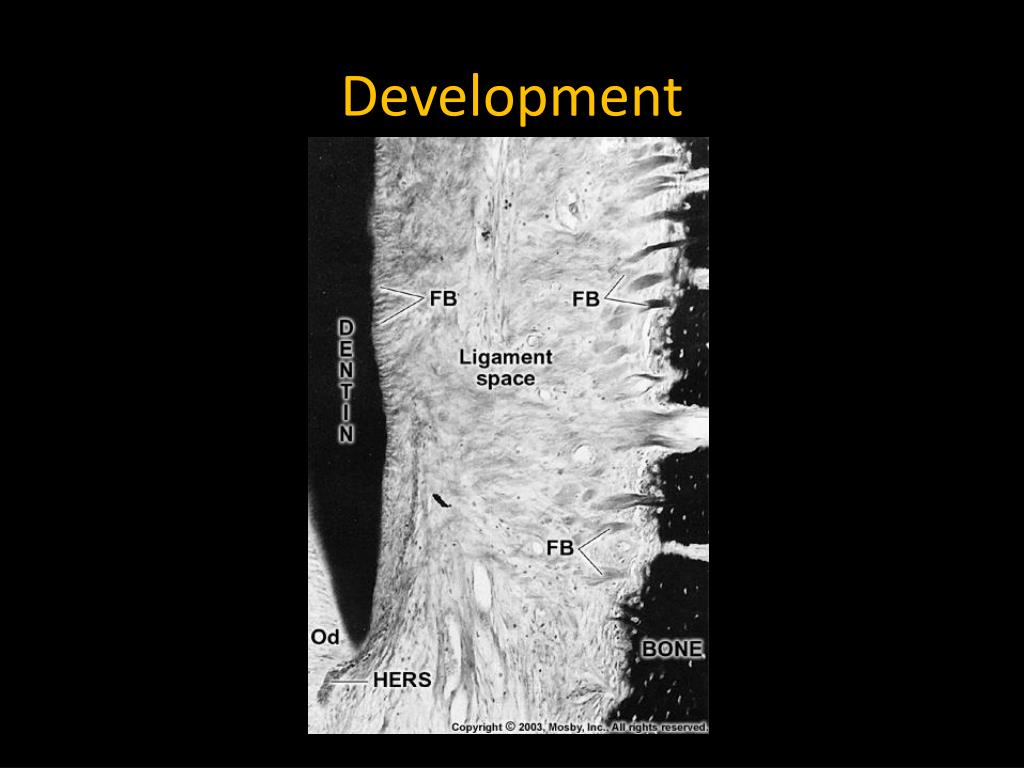

4. Development